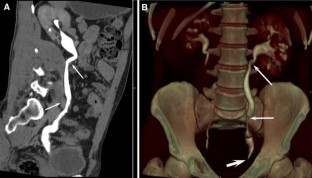

The combination of EU + CT correctly diagnosed 38 out of the 39 cases with a sensitivity of 97%. Correct diagnosis was established in all malignant cases (n = 17) but one benign case consistent with blood clots in the upper urinary tract was incorrectly diagnosed as a multicentric urothelial carcinoma. Sensitivity, specificity, and accuracy for the diagnosis of the underlying cause with EU + CT was 100%, 95%, and 97%, respectively. The final diagnoses were: urothelial carcinoma (n = 10), stone disease (n = 10), bladder tumor (n = 4), benign post-treatment ureteral stenosis (n = 4), ureteral invasion (n = 3), benign bladder disease (n = 2), urinary tract infections (n = 2), crossing vessels (n = 1), ureteropelvic junction obstruction (n = 1), retrocaval ureter (n = 1), and blood clots in the upper urinary tract due to bleeding renal metastasis from lung cancer (n = 1).

Combined EU and CT study allowed correct diagnosis of the underlying cause of delayed excretion or upper urinary tract dilatation in 97% of cases. The combination of EU and CT provides diagnosis reducing time and radiation.